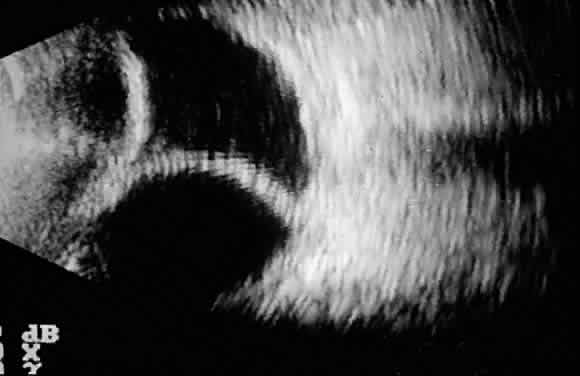

Postoperative suprachoroidal hemorrhage usually occurs within the first week after glaucoma surgery and usually is associated with postoperative hypotony4–6 (Fig. 1). The development of a suprachoroidal hemorrhage typically is acute and associated with the sudden onset of severe pain. Examination of the anterior segment frequently reveals a shallow anterior chamber and a normal or high intraocular pressure (IOP). On fundus examination, a detached and dark choroid is noted. The choroidal elevations have a dark, reddish brown color. Some patients present with bleeding into the vitreous cavity and, uncommonly, retinal detachment. Ultrasonography can be used to diagnose suprachoroidal hemorrhage when fundus examination is not possible.

Fig. 2. Composite of ultrasound biomicroscopic examination. A peripheral choroidal effusion (large arrow) is seen as an acoustically hollow area in the suprachoroidal space. The anterior chamber is moderately shallow (small arrow, intraocular lens).

Fig. 4. B-scan ultrasound showing hyperreflective dome-shaped echoes corresponding to the detached choroid-retina, with acoustically hollow content corresponding to the fluid accumulated in the suprachoroidal space.